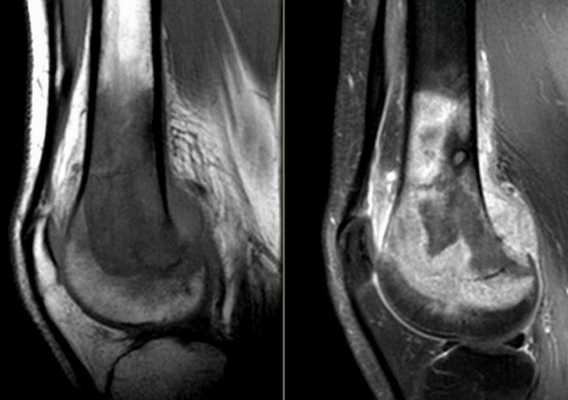

Диагностика диабетической остеоартропатии основывается на комплексной оценке клинической картины, визуальном осмотре пораженной стопы, анамнезе заболевания и обследованиях, включающих анализ работы нервной, эндокринной и опорно-двигательной системы. К основным методам относятся:

1. Рентгенография стоп в 2-х проекциях (прямой и боковой). Выявляет признаки разряжения костной ткани, определяет уровень минерализации костей.

2. Магнитно-резонансная и компьютерная томография стоп . МРТ стопы позволяет визуализировать изменения мягких тканей, микротравмы и микротрещины на начальных стадиях болезни. КТ оценивает степень деструкции кости, поражение надкостницы.